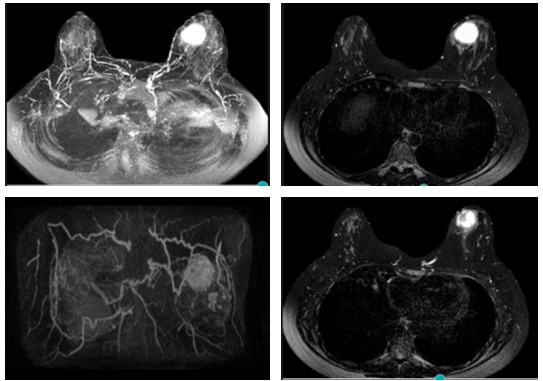

Características radiológicas en resonancia magnética

En la resonancia magnética estos tumores suelen exhibir características morfocinéticas que sugieren lesiones malignas. La mayoría de los estudios proporcionan información relevante para el análisis de las características morfológicas de los CMTN. Por lo general se presentan con alta señal en secuencias potenciadas en T2 e imágenes STIR (Short Time Inversion Recovery), principalmente centrales, lo que es indicativo de necrosis.(30)

En el estudio dinámico tras la administración de contraste intravenoso, estos tumores se manifiestan como áreas de captación tipo “masa” de aspecto heterogéneo, con realce de predominio periférico y engrosamiento cutáneo asociado. Las curvas de captación son en su mayoría tipo 2 o indeterminadas y tipo 3 (realce intenso con lavado posterior), con bajos niveles de Apparent Diffusion Coefficient (ADC), se acompañan de metástasis ganglionares en el 75% de los casos.(5, 10, 22, 23, 24, 25, 26, 27)

En estudios de resonancia magnética se identificaron hallazgos altamente sospechosos, caracterizados por nódulos hiperintensos en T2 con realce al contraste en forma de anillo y una curva de lavado (wash out) en tiempo tardío.

En ecografía evidenciaron que se expresa como nódulo redondeado u oval, de márgenes circunscritos, hipoecoico con refuerzo acústico posterior en algunas ocasiones categorizado como BI-RADS 3. En resonancia magnética se visualizaron como nódulos de márgenes irregulares, con realce nodular poscontraste en anillo, con curvas anormales en fase tardía tipo “wash out”.

En las mamografías se observaron nódulos con morfología irregular, seguidos de los lobulados, sin asociación con calcificaciones, y con una mayor afectación en la MI, específicamente en CSE. En las ecografías, la presentación más común fue un nódulo de morfología lobulada, seguido de cerca por nódulos irregulares, siendo hipoecoicos en el 99% de los casos, con orientación antiparalela y sin hallazgos acústicos posteriores. En la resonancia magnética, el hallazgo predominante fue la presencia de una masa con realce anular y una curva cinética tipo III en fase tardía.

Características en RNM del CMTN

En los resultados de las características en resonancia magnética, se debe tener en cuenta que de las 17 pacientes solo se dispone información de 8 resonancias magnéticas realizadas en centros periféricos. Esto representa el 75% de la muestra, equivalente a 8 casos.

De estos casos se destaca que informan una cantidad de tejido fibroglandular tipo B, aunque no describen el realce parenquimatoso de fondo ni hallazgos asociados.

En lo que respecta a la descripción nodular, se encontró que en el 77,7% de los casos (7 de 8) el nódulo se reportó como redondeado, seguido de la forma ovalada.

Los márgenes del nódulo en 7 casos se describen como circunscritos y solo en 1 caso se reporta como espiculado.

Según lo referido realce interno del nódulo, 5 casos presentaron realce heterogéneo periférico y 3 casos mostraron un realce en forma de anillo.

Finalmente, en la evaluación de la valoración de las curvas cinéticas, se notó que en la fase inicial los 8 casos tenían una fase rápida. En la fase tardía, 6 de los casos presentaban un patrón de wash out, mientras que 2 casos mostraban un tipo de realce en meseta.

Anexo 3. Imágenes CMTN en resonancia magnética